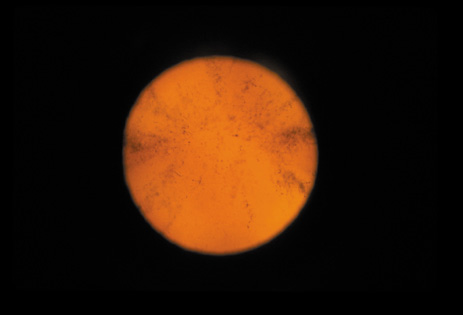

Cortical opacities have been clinically observed to develop earliest in the inferior half of the lens, especially the lower nasal quadrant.28 Epidemiologic29 and laboratory studies30 have suggested that cortical cataracts may be caused by ultraviolet rays from sunlight. The supraorbital margins may block the ultraviolet rays from falling over the upper part of the lens, thus making cortical cataract less frequent in the upper quadrants. Eventually these opacities also develop in the periphery in other quadrants, resulting in a circular array of spokes and peripheral cuneiform opacities (Fig. 9). Bands of central cortical fibers may become prominent and opacify centrally (Fig. 10). However, most cortical cataracts remain in the periphery for many years, even decades, before the central axis of the lens becomes involved, causing loss of vision late in the development of the cataract.

Fig. 9. Moderate cortical changes. Wedge-shaped (cuneiform) or spoke-like (wheel) peripheral changes are seen. These changes may be extensive but may not affect Snellen visual acuity since they occur in the periphery.